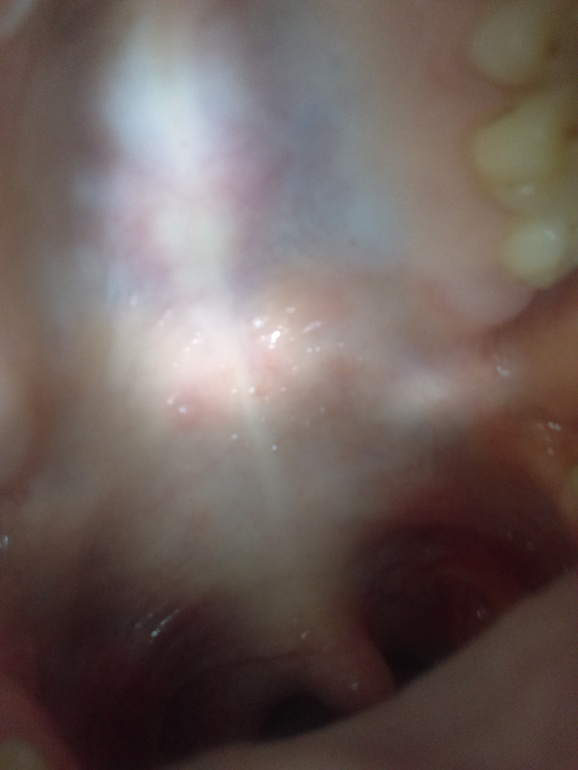

Аня 8 лет Всем привет, у меня проблема переодическии во рту на необе лезет как прыш балит похож на герпес гриб Посмотрите еще 20 записей на эту тему Отменить Ответить Margo https://www.pro-zuby.ru/parodontologiya/polost-rta/pryshchi-vo-rtu.html 22.04.2018 Ответить Аня вот так это выгледет спасиба 22.04.2018 Ответить Галина Вам надо к стоматологу сходить. Он назначит лечение. 22.04.2018 Ответить Тут токая проблема на 28 день цикла делала тест одна полоска ,цикл у меня 30 дней сеглдня 32 а месеч Чаты Беременных Выберите чат: Январята-2026 Февралята-2026 Мартята-2026 Апрелята-2026 Майчата-2026 Июнята-2026 Июлята-2026 Августята-2026